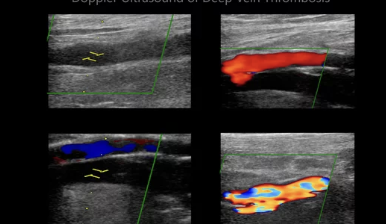

하지정맥 초음파 검사는 하지정맥류 진단의 가장 기본적이고 중요한 검사입니다. 혈관 초음파를 통해 다리 정맥의 상태, 혈액 역류 여부, 혈전 유무 등을 확인하여 정확한 진단을 내릴 수 있습니다.

하지정맥류는 초기에는 증상이 경미하여 방치하기 쉽지만, 조기에 발견하고 치료하지 않으면 만성 정맥 부전, 피부염, 궤양 등 심각한 합병증으로 이어질 수 있습니다. 따라서 다리 부종, 통증, 저림, 피부 변색 등의 증상이 나타난다면 반드시 하지정맥 초음파 검사를 받아보는 것이 좋습니다.